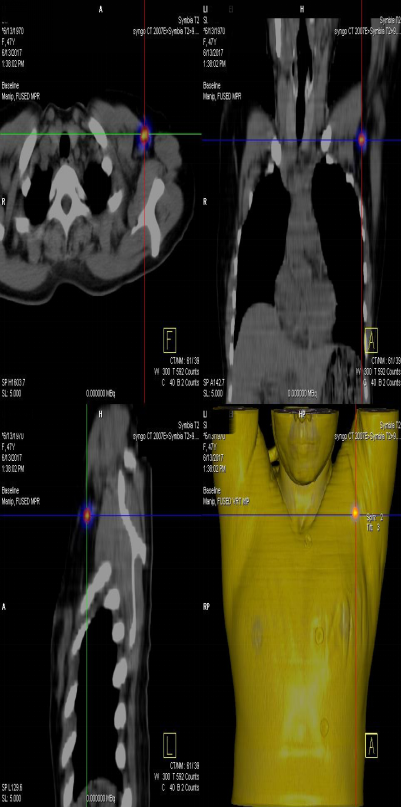

前哨淋巴結(jié)顯像技術(shù)一般在腫瘤附近注射放射性核素標(biāo)記特殊藥物,這種藥物會(huì)被前哨淋巴結(jié)攝取,存在于前哨淋巴結(jié)中。24小時(shí)之內(nèi)都可用SPECT-CT進(jìn)行前哨淋巴結(jié)顯像檢查。

找到幾個(gè)淋巴結(jié)沒(méi)有明確的限制,淋巴結(jié)核素計(jì)數(shù)小于第一個(gè)SLN計(jì)數(shù)的10%就不再是前哨淋巴結(jié)了。

患者李女士,發(fā)現(xiàn)右側(cè)乳腺腫物,來(lái)我院就診,行乳腺腫物局部擴(kuò)大切除術(shù),術(shù)后病理回報(bào):右乳腺浸潤(rùn)性導(dǎo)管癌III級(jí),伴原位癌。擬行右乳腺癌切除術(shù),提檢前哨淋巴結(jié)顯像檢查,明確有無(wú)淋巴結(jié)轉(zhuǎn)移。